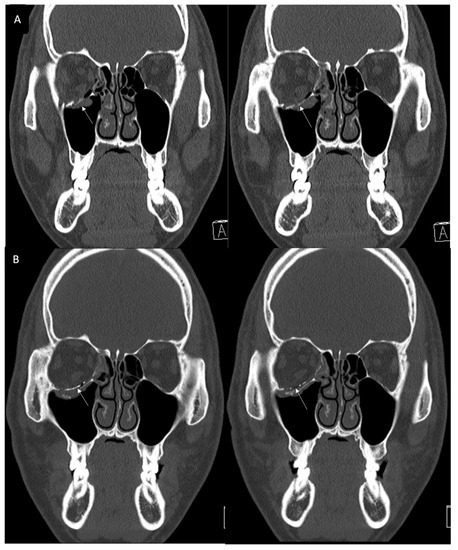

3.2. Case 2

A 48-year-old female patient came to our clinic with left eyeball swelling and ecchymosis caused by a car accident. The patient complained of pain and discomfort with eyeball movement (Figure 3). We surgically approached the medial orbital wall fracture seven days after the accident. After the subciliary incision, the fracture was exposed. The titanium-reinforced porous polyethylene (TR-PPE) plate was placed on the fracture site using a single screw at the inferior orbital rim (Figure 4). The patient was discharged on postoperative day 2 with significantly improved pain and discomfort.

Figure 3. Case 2. Preoperative facial CT scan (coronal view) of the 48-year-old female patient with left inferomedial orbital wall fracture. The titanium-reinforced porous polyethylene (TR-PPE) plate was placed on the inferomedial orbital wall using a single screw at the inferior orbital rim. (White arrow).

Figure 4. Case 2. Follow up facial CT finding (coronal view) of the same patient. The titanium-reinforced porous polyethylene (TR-PPE) plate was placed on the inferomedial orbital wall using a single screw at the inferior orbital rim. (White arrow).